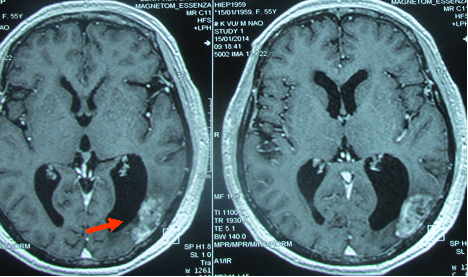

MRI sọ não: u não nhỏ, giảm chèn ép (hình 4).

Trước điều trị

Sau điều trị

Hình 4: Hình ảnh chụp MRI sọ não sau 6 tháng cho thấy sau hóa chất Navelbine và xạ trị toàn não u não thu nhỏ nhiều, kích thước còn (1,8x2,5)cm.